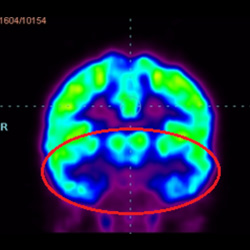

細(xì)胞治療后,藍(lán)色和黑色區(qū)域減少,并且看到更活躍的區(qū)域。這表明損傷減少并改善了大腦功能。